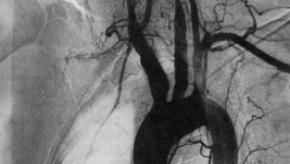

Several studies were reported at EULAR2023 about Takayasu’s arteritis (vasculitis), a very rare large vessel vasculitis that occurs in young individuals.